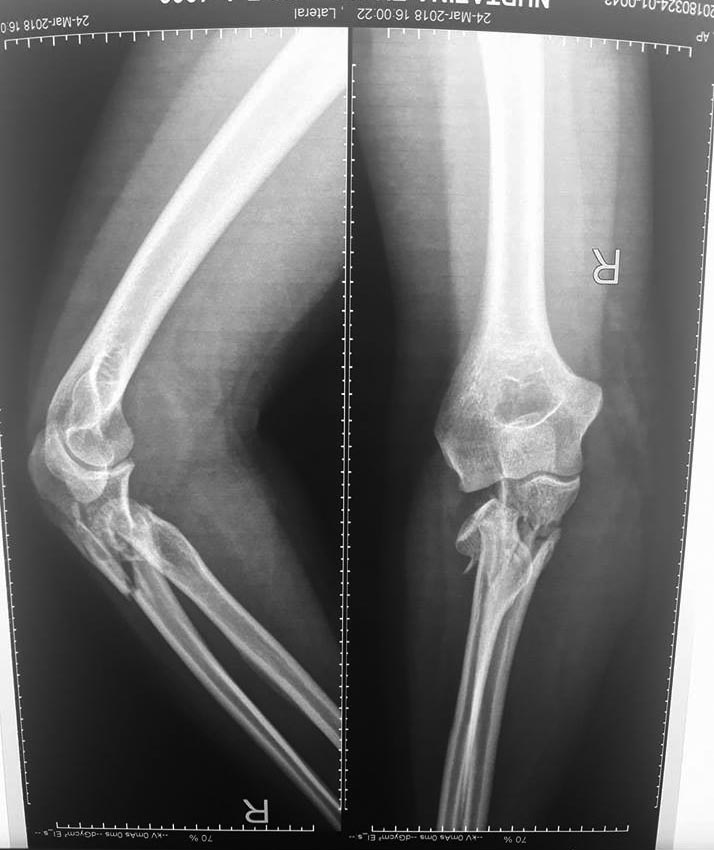

Добрый день, коллеги. Какие мнения будут по этому снимку?

А так, здесь имеется многофрагментарный проксимальный перелом локтевого отростка с переломо-вывихом головки лучевой кости по классификации Mason III. Решение принимается на основании КТ срезов, потому что на боковом рентген снимке вроде отсутствует смещение, где сустав и контур Coronoid в одном блоке, а на прямом подозрение на смещение в Coronoid?

Для перелома локтевого отростка придуманы много пластин, надо выбрать по длине. А при краевых переломах головки ее окружность можно восстановить винтами 2 мм, но в данном случае имеется полный вывих головки и фиксация, даже специальной пластиной, может осложнится. Протез головки после удаления предупреждает нестабильность в суставе и деформацию оси конечности в будущем!

Конверсионные спицы на уровне проксимального отдела лучевой кости интересная идея, но на уровне перелома в области шейки трудно удержать головку. Предварительная репозиция локтевого отростка с временной установкой пластины, затем удаление экономит время. Доступ через локтевой отросток, где можно фиксировать или удалить головку с замещением, а потом установить пластину обратно на локтевой отросток!